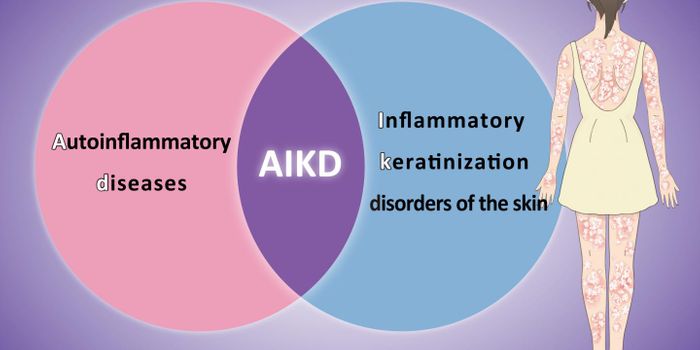

FEB 02, 2024Genetics & GenomicsMillions of people have autoimmune diseases, such as multiple sclerosis or rheumatoid arthritis but it's estim ...